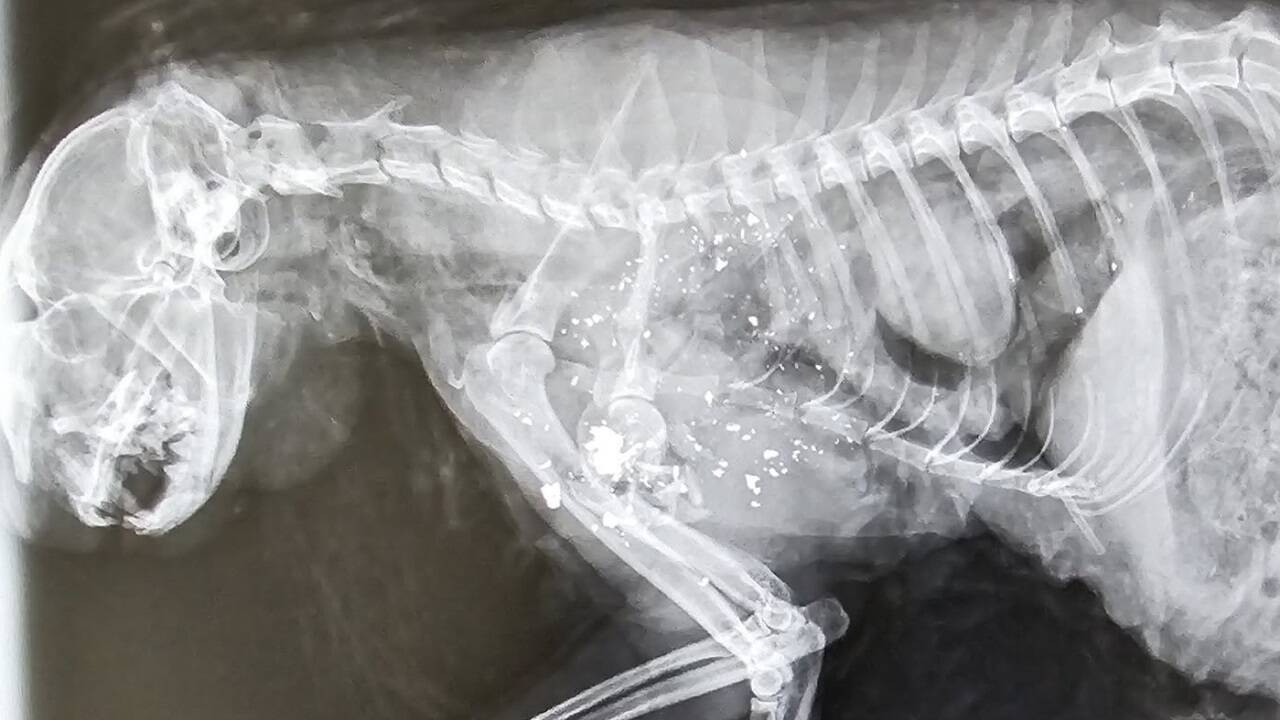

Nachdem in der Bergsiedlung von Eben eine tot aufgefundene Katze eindeutige Schrotverletzungen aufwies, ermittelt nun die Polizei. Die Tierhilfe spricht von keinem Einzelfall.

Im Brustbereich seien laut Angaben der Tierhilfe Schroteinschüsse zu sehen.